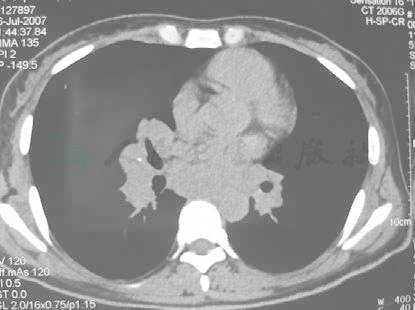

WBC 4.13×109/L, N 43.1%, E 6.31%;血细胞沉降率20mm/h;彩超:腹腔、双侧锁骨上及右侧腹股沟均可见肿大淋巴结。肝脏彩超示:肝实质回声略细,肝左内叶见大小1.5cm×1cm结节样低回声,轮廓清。7月6日肺CT示双肺纹理增强、紊乱,双侧肺野内可见多发、弥漫性分布的大小不等的结节影,大部分结节沿支气管走行分布,右肺内可见多发淡片状密度增高影。双侧肺门影增大,可见多发结节影,气管及主支气管壁可见多发小结节状突起影,部分支气管变窄。纵隔内可见多组肿大淋巴结影(图2)。

图2-1 肺CT示双侧肺野内可见多发、弥漫性分布的大小不等的结节影,双侧肺门影增大,可见多发结节影,气管及主支气管管壁可见多发小结节状突起影,纵隔内可见多组肿大淋巴结影(2007-07-06)

图2-2 肺CT示双侧肺野内可见多发、弥漫性分布的大小不等的结节影,双侧肺门影增大,可见多发结节影,气管及主支气管管壁可见多发小结节状突起影,纵隔内可见多组肿大淋巴结影(2007-07-06)